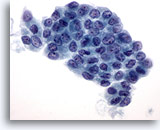

Positief voor maligniteit

Bij de monsters in deze categorie geldat dat bij resectie in bijna 100% van de gevallen een maligniteit wordt gevonden. Papillair carcinoom is de meest voorkomende maligniteit van de schildklier en heeft specifieke nucleaire kenmerken die eenvoudig zijn vast te stellen bij cytologische monsters. Andere maligniteiten waarvan de diagnose zeer nauwkeurig kan worden vastgesteld op basis van cytologie, zijn onder andere medullaire carcinomen, lymfomen, en metastatische carcinomen. Papillair carcinoom wordt gekenmerkt op ThinPrep door lagen en papillaire clusters van opeengepakte cellen met kernvergroting en molding, poederige chromatine, onregelmatige kerncelmembranen (met name kerngroeven en intranucleaire cytoplasmische inclusies), en kleine maar prominente en vaak eosinofiele nucleoli.[7] Daarentegen wordt medullair carcinoom gekenmerkt door geïsoleerde monomorfe plasmacytoïde cellen, die een hoge kern/cytoplasma-ratio hebben, excentrische kernen en grofkorrelige chromatine met of zonder een prominente nucleolus. Kleine, onopvallende granulen vullen het cytoplasma. Soms lijken de cellen spoelvormig, maar vertonen ze dezelfde nucleaire kenmerken. Lymfomen en metastatische carcinomen van de schildklier komen veel minder vaak voor. Hun cytologische kenmerken hangen af van het type en de plaats van oorsprong.